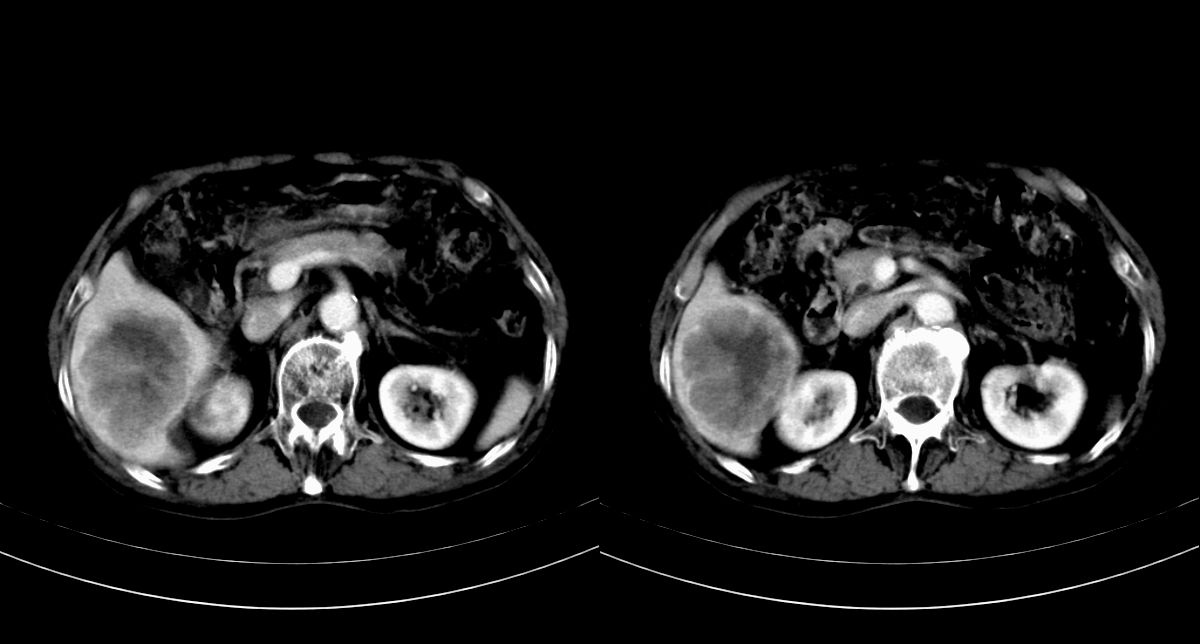

男,79y,无不适。体检发现肝脏占位。

肝内多发低密度结节,增强动脉期明显强化,门脉期逐渐下降,内有液化坏死区。

肝内多发低密度结节灶,增强动脉期明显不规则环状强化,;门脉期逐渐下降,肿瘤壁厚薄不一,内有坏死液化区。